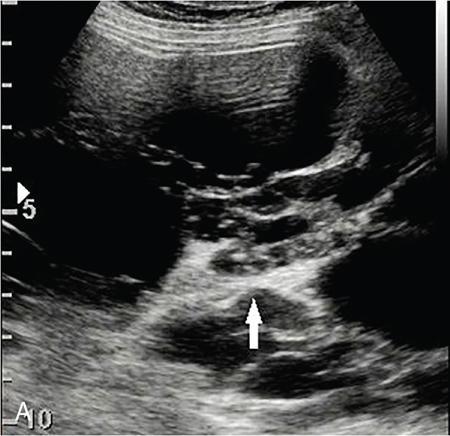

Drushi Patel CONTRAST-ENHANCED ULTRASOUND IN ADULT GENITOURINARY IMAGING Mridula Muthe Ultrasound is the initial screening examination for the evaluation of the renal morphology and suspected renal lesions due to its multiple advantages such as easy accessibility, bedside assessment, affordability and lack of radiation. Vascularity of the kidney and renal lesions can be studied with the use of colour Doppler ultrasound however, it provides information only about the macrovasculature. With the use of microbubble ultrasound contrast agents (UCAs) macro as well as the microvasculature can be studied. Contrast-enhanced ultrasonography (CEUS) is also more sensitive than Doppler ultrasound as it is not affected by blood velocity and angle of insonation of the ultrasound beam. In urology, the established applications of CEUS in adults include characterization of cystic lesions and differentiation between pseudotumours and solid lesions. Box 10.23.1.1 provides a list of European Federation of Societies for Ultrasound in Medicine and Biology (EFSUMB) recommended indications of CEUS in renal evaluation. EUROPEAN FEDERATION OF SOCIETIES FOR ULTRASOUND IN MEDICINE AND BIOLOGY (EFSUMB) RECOMMENDED INDICATIONS FOR USE OF UCA IN RENAL EVALUATION Renal ischaemia. Evaluation of solid renal lesions. Differentiation between solid renal lesions and pseudotumours. Characterization of complex cystic masses. Characterisation of indeterminate renal masses. Renal infections. Follow-up of nonsurgical complex masses. To improve lesion visualization in patients undergoing renal tumour ablation under US guidance and to detect residual tumour either immediately or after ablation. Isolated blunt moderate-energy renal trauma. Follow-up of trauma patients managed conservatively. Characterization of thrombus in renal vein and inferior vena cava. In patients with contraindications for CT- and MRI-based contrast media. Evaluation of lesions in transplant kidneys. Evaluation of ischaemia and vascular complications in transplant kidneys. Tumour response assessment to biologic therapy. Intracavitary CEUS for guiding percutaneous nephrostomy. Source: P.S. Sidhu, V. Cantisani, C.F. Dietrich, O.H. Gilja, A. Saftoiu, E. Bartels, et al., The EFSUMB guidelines and recommendations for the clinical practice of contrast-enhanced ultrasound (CEUS) in non-hepatic applications: update 2017 (long version). Ultraschall in der Medizin-Eur. J. Ultrasound 39 (02) (2018) e2–e44. CEUS involves the intravenous injection of UCAs consisting of gas microbubbles. These UCAs remain purely in the intravascular compartment as they are small enough to avoid filtration by the lungs and too large to enter the interstitial compartment. UCAs cause marked amplification of signals from the flowing blood, thus providing information about the microvasculature and parenchymal perfusion. Sonovue is a second-generation UCA and is the only UCA available in India. It consists of sulphur hexafluoride gas which is exhaled by the lungs and is surrounded by phospholipid monolayer which is metabolised by the liver, making it safe for patients with renal insufficiency. For renal evaluation, a dose of 1–1.5 mL of Sonovue is administered as a bolus dose followed by a 10 mL saline flush. CEUS is performed on machines with contrast-specific software’s using a low mechanical index (MI) technique. The use of a dual image display is beneficial for the evaluation of small lesions. A conventional B-mode ultrasound is first performed to acquire measurements, assess morphology and to detect focal lesions along with Doppler ultrasound to assess vasculature. However, due to limitations in the assessment of focal lesions, microvasculature, complex cysts, poor contrast between the lesion and cortex or medulla, it is preferable to perform a CEUS study for additional characterization. The enhancement pattern of the kidney is different than that of the liver due to the dual blood supply of the liver as opposed to afferent arterial supply and efferent venous drainage of the kidney. After an intravenous bolus of UCA, kidneys show intense enhancement. Contrast is first seen in the main renal artery, followed by its branches. CEUS has only two enhancement phases, that is cortical phase which lasts for 15–30 seconds and a parenchymal phase (enhancement of both cortex and medulla) for 25 seconds–4 minutes after UCA administration. The renal cortex enhances first, followed by the outer medulla which is followed by gradual enhancement of the pyramids (Fig. 10.23.1.1). During the washout phase first, there is a reduction in the medullary enhancement followed by a slower washout of the cortex. As kidneys don’t excrete UCAs, there is no opacification of the pelvicalyceal system. UCAs can act as a problem-solving tool in patients with renal failure as they are not nephrotoxic. Due to its excellent ability to depict renal vascularization, it can be used for detecting perfusion abnormalities. CEUS is useful for detecting vascular causes of renal function deterioration. Renal infarcts appear as wedge-shaped nonenhancing areas in all phases. Renal infarcts show a focal complete lack of parenchymal enhancement on CEUS whereas ischaemic areas show reduced enhancement. CEUS can confidently differentiate infarction from cortical necrosis by the demonstration of preserved hilar vascularity in the latter. Renal pseudotumours such as foetal lobulations, dromedary hump, parenchymal hypertrophy due to renal scarring and column of Bertini can be accurately differentiated from true tumours using CEUS. Pseudotumours show similar enhancement to the adjacent parenchyma and appear isoechoic on all phases while true tumours show different enhancement pattern on at least one phase (Fig. 10.23.1.2). True tumours will cause mass effect and distort the normal vascular architecture of the renal parenchyma whereas in pseudotumours the vascular architecture is preserved. In addition, the identification of medullary pyramids within the mass points towards it being a pseudotumour rather than a true mass. Cysts can be categorized according to the Bosniak classification using CEUS. Due to its superior spatial and temporal resolution, CEUS is considered superior to CT for detecting additional septations, wall or septal thickening and solid components (Figs 10.23.1.3–10.23.1.5). CEUS allows for real-time imaging of blood flow within the septae, wall or nodules within the cysts which may not be seen on CT or MR imaging. The sensitivity of CEUS is comparable to CT for the classification of renal cystic lesions as benign or malignant however, it is not as useful for staging. The follow-up of inoperable complex cystic lesions is better performed with CEUS rather than CT due to the absence of ionizing radiation. Complex cysts or masses with calcifications are not suitable for evaluation with CEUS. CEUS allows a detailed evaluation of the circulation in mass lesions as it demonstrates the macro as well as microvascular enhancement patterns. CEUS has more sensitivity than CT for detecting blood flow in hypovascular lesions. It can also be used to distinguish between complex cysts and solid lesions which remain equivocal on CT and ultrasound (B-mode and colour Doppler). CEUS is sensitive in identifying cystic areas, necrosis, debris and haemorrhage in small tumours that may be difficult to visualize on CECT and MR. Isoechoic lesions on conventional ultrasound are better characterized by CEUS (Fig. 10.23.1.6). Hyperdense renal lesions on noncontrast CT (NCCT) with HU values between 20 and 70 are better evaluated by CEUS which can classify these lesions as solid or cystic. CEUS can suggest the histological subtype of tumours. Clear cell carcinomas show heterogeneous hyperenhancement in the cortical phase and rapid washout along with a peripheral enhancing rim or pseudocapsule seen during the parenchymal phase. Papillary carcinoma shows progressive heterogeneous enhancement during the cortical phase and displays hypoenhancement as compared to the cortex on all phases. Malignant renal vein thrombus will show enhancement as compared to bland thrombus on CEUS. Tumours that are smaller than 3 cm commonly show homogeneous enhancement, regardless of their histologic subtype. Differentiation between angiomyolipoma, renal cell carcinoma and oncocytoma is not always possible. Although, CEUS has excellent sensitivity for the detection of malignancy, it has a higher false-positive rate as compared to CECT. Hence, combined use of CEUS for its high sensitivity and CECT for its high specificity may be performed for an accurate diagnosis. CEUS is effective in patients with complicated pyelonephritis, for identifying inflammatory parenchymal involvement, characterized by round or wedge-shaped hypovascular parenchymal areas, most conspicuous during the late parenchymal enhancement phase. An abscess is seen as a nonenhancing area, with or without peripheral or septal enhancement. CEUS can also be used for the follow-up of renal abscesses. All the aforementioned indications of CEUS in native kidneys also apply to renal transplants. Infarction, vascular complications such as arterial and venous thrombosis can be detected. Quantitative CEUS for assessment of graft dysfunction is a subject of active research. CEUS can be used as an alternative to CT especially in children with isolated blunt moderate energy injuries who are hemodynamically stable. It can also be used in the follow-up of conservatively managed trauma patients and in renal impairment. During Focused Assessment with Sonography for Trauma (FAST), the examination should begin with the kidneys as they have a fleeting enhancement. The kidneys are studied in the arterial phase with two separate doses administered for either kidney during FAST. On CEUS, lacerations, hematomas, and infarcts are seen as nonenhancing areas on late-phase images whereas contusions may show faint enhancement. Pseudoaneurysms and active bleeding are diagnosed on the arterial phase. Crucial complications such as devascularized parenchyma and acute cortical necrosis can also be diagnosed on CEUS. Pelvicalyceal system injury cannot be detected by CEUS as UCAs are not excreted by the kidneys. CEUS can be performed in conjunction with percutaneous ablation therapies. Preablation evaluation with CEUS is essential to assess lesion vascularity and to compare pre and postprocedure tumour viability. Also, the identification of a pseudocapsule predicts improved ablation efficacy. CEUS has demonstrated high sensitivity, specificity and accuracy for the early detection of residual unablated tumour. Dynamic contrast-enhanced ultrasound is a useful tool for early identification of responders and nonresponders, enabling tailoring of the treatment regimen. It is performed by two methods – Bolus injection of a UCA with time-intensity curve analysis (commonly used) and intravenous injection of UCA with disruption–replenishment analysis. In patients with chronic kidney disease, the contrast enhancement is less intense and fades earlier as compared to a normal kidney. CEUS aids in characterizing renal lesions in patients with renal failure. Characterization of lesions with indeterminate appearances in patients with renal dysfunction, on conventional US prevents unnecessary further evaluation with contrast-enhanced CT or MRI and further deterioration of the renal function as well as unwarranted investigations. CEUS nephrostomogram can be performed after percutaneous nephrostomography to confirm the correct positioning of its tip, detect the site of obstruction and to diagnose complications. UCAs can be safely administered in patients with minimal risk. They can be safely administered in patients with renal insufficiency as they are not excreted by the kidneys. Prior laboratory tests are not indicated as they are not nephrotoxic and don’t interact with thyroid function. Most adverse effects are mild such as nausea, headache, chest discomfort, chest pain and resolve spontaneously. The contraindications include known hypersensitivity, patients with right-to-left shunts, severe pulmonary arterial hypertension (pulmonary arterial pressure >90 mm Hg), uncontrolled systemic hypertension, and respiratory distress. The rate of anaphylactic reactions is significantly lower than iodinated contrast media and comparable to gadolinium-based contrast agents. Caution should be exercised in patients with severe acute coronary disease and in patients with unstable angina. CEUS is a rapidly evolving technique, can be conveniently performed as an extension of conventional ultrasound and acts as a valuable tool in the characterization of indeterminate renal lesions, especially when the lesion is small. The advantages of CEUS include quick assessment, real-time imaging, high contrast resolution, excellent safety profile, lack of ionizing radiation, great repeatability, and most importantly, ideal for contrast evaluation in patients with deranged renal function. DUAL-ENERGY AND SPECTRAL IMAGING IN GENITOURINARY SYSTEM Aditi Chaitanya Gujarathi-Saraf Dual-energy CT (DECT) also known as ‘spectral imaging’, was first conceptualized in the 1970s. However, the clinical applications of DECT have recently emerged as owing to improvements in postprocessing techniques. The development of a single-detector, single-source DECT (ssDECT) with the capability for rapid alternation between two peak voltage settings (‘fast switching’) and a dual-detector, dual-source DECT (dsDECT) system in last few years have made possible various applications in solving clinical problems. In DECT, the simultaneous use of two different X-ray beam energy settings (80 and 140 kVp) allows the differentiation of materials on the basis of their attenuation characteristics (material density). There are two major applications of DECT in genitourinary system. First being characterization of renal calculi to differentiate those containing uric acid (UA) from those which do not. The other application is to characterize small renal masses which include differentiating complex cysts from renal tumours, detection of solid growth in PCKD patients and detection of residual tumour after thermal ablation of a renal neoplasm. The principle of DECT imaging is based on the differential absorption of X-ray energy at variable kVp settings. In DECT, two energy levels (typically 80 and 140 kVp) are used to acquire images that can be processed to generate additional datasets. Thus, a tissue or any material in the body shows different degrees of attenuation when scanned at different X-ray energies. Conventional CT numbers (attenuation measurements in Hounsfield units) are related to the linear attenuation coefficient of a particular material. The unique linear attenuation coefficients obtained by imaging at two different energies can be used to discriminate between different materials (e.g. fat, calcium, iodine and water). The characterization of material on DECT depends on their CT number ratio (CTR) also called dual-energy ratio. DE RATIO = CT number of a given material in the low-energy image CT number of the same material in the high-energy image DECT and spectral CT can be performed by three techniques (Fig. 10.23.2.1): Two sets of material-specific images are created to detect the presence or absence of a material. The two basic materials selected should have significant difference in mass attenuation coefficients and atomic number. The two commonly selected pairs are: Iodine-specific images are most commonly used in the clinical practice. When iodine is paired with water, two separate image data sets are generated. On water density image, the voxels that show change in attenuation due to presence of iodine are removed. These are instead represented on iodine density images. Thus, virtual unenhanced images are generated which resemble the conventional unenhanced images. Renal calculus disease is a common disease affecting approximately 10%–14% of population in India commonly affecting 31–45-year-old patients. Accurate diagnosis of composition of renal calculi is crucial as the frequency of prevalence and recurrence rate of renal calculi is high in most states of India. The obstructing calculi can lead to obstructive uropathy, pyelonephritis, urinary sepsis with nearly 50% of the patients being affected by renal failure. There are multiple compositions of renal calculi, most common being calcium oxalate (70%), calcium phosphate (20%), uric acid (8%) and cystine (2%). In general, UA calculi have lower attenuation values than nonuric acid calculi (i.e. struvite, cystine and calcium) on conventional CT. However, it may be difficult to distinguish between the two due to overlap in attenuation values. Here DECT becomes a problem-solving tool as it uses the two-material differentiation approach. Thus, in addition to size and location, DECT provides information about the composition of calculi to the urologist. DECT has high sensitivity of 88%–100% and high accuracy of 93%–100% to differentiate UA calculi from nonuric acid UA calculi. This is of utmost clinical importance as UA calculi can be treated medically whereas non-UA calculi require invasive methods of treatment such as extracorporeal shockwave lithotripsy (ESWL) or percutaneous nephrolithotripsy (PCNL). In clinical practice, NCCT scan of KUB region is performed at 80 and 140 kVp to generate two image datasets and obtain the DE ratio. A cut-off value of DE ratio of 1.2 is used to differentiate UA calculi from non-UA calculi (Fig. 10.23.2.2). Following flow chart shows differentiation of renal calculi based on DE ratio.